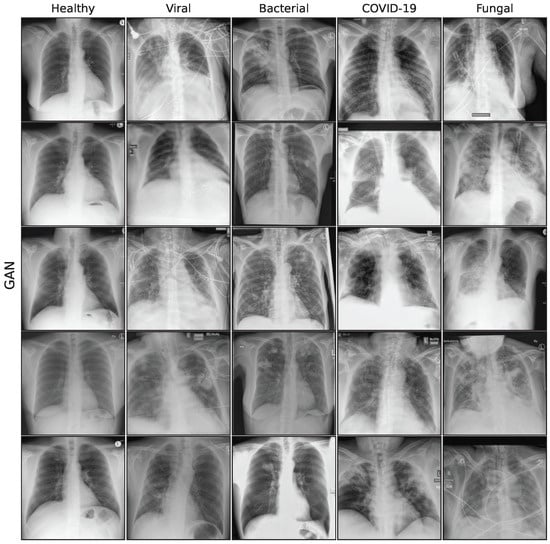

Figure A7. Sample synthetic images from DreamBooth model for all classes.

3.2.5. DreamBooth

DreamBooth [43] is a specified method to personalize text-to-image diffusion models with new subjects in a few-shot manner. Similar to standard fine-tuning, the approach fine-tunes the U-Net component on domain-specific images, while keeping the autoencoder and text encoder frozen. To prevent catastrophic forgetting and adapt to new concepts, a prior-preserving loss is used, which pairs images and prompts from the prior [43]. This technique enables the generation of high-fidelity CXR images with simple pathologies through text conditioning. However, overfitting can still occur, and image diversity remains limited. Therefore, the number of training iterations are limited. Figure A7 in the Appendix A shows a collection of synthetic images for the DreamBooth model.